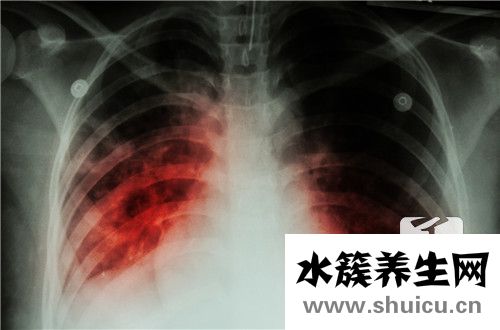

我相信許多人都熟悉肺結(jié)核這種疾病。許多人提到這種疾病,甚至非常害怕。鈣化后,這種疾病也會影響肺結(jié)核患者本身。許多肺結(jié)核患者想知道他們的胸部在沒有鈣化之前是否會有鈣化的感覺。那么,肺結(jié)核鈣...